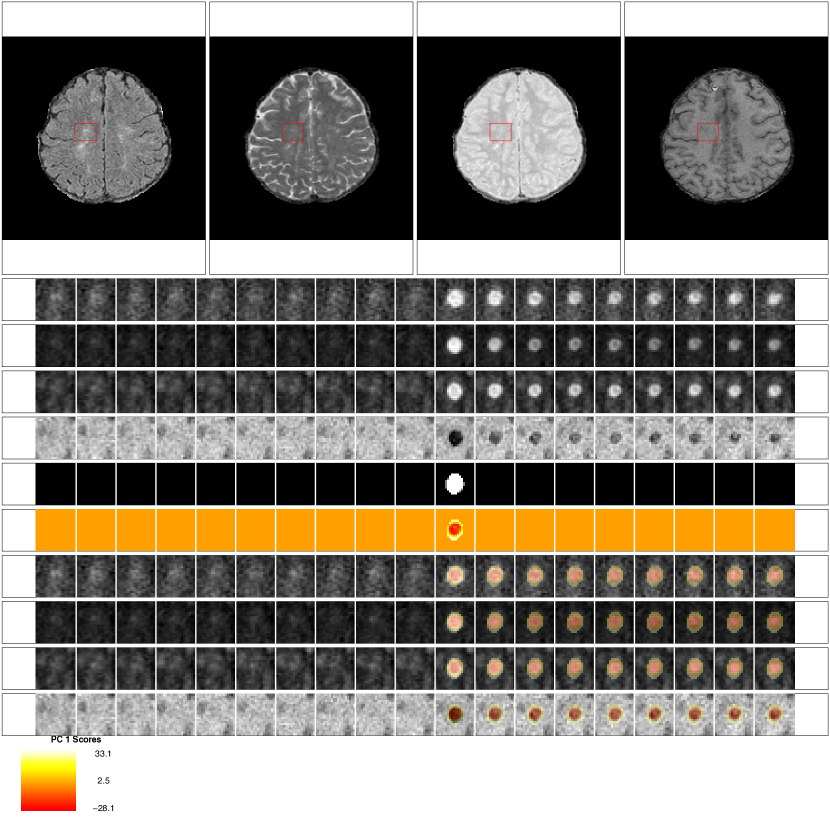

Figure 2 shows an example of a lesion that is detected during a subject’s follow-up period. The first row of Figure 2 shows the multiple MRI sequences at one time point (from left to right, the FLAIR, T2, PD, and T1 sequences). In each sequence, a red box shows an area with a lesion that develops during the follow-up period. The subsequent 4 rows of the figure show the longitudinal behavior within this red box. Each column of the figure shows a different MRI study, starting at 98 days after baseline in the far left column and going until 343 days after baseline. The lesion in the red box is first seen 175 days after baseline.

Figure 2: Longitudinal MRI studies within lesions. The first row of the figure shows an axial slice from the multiple MRI sequences, 175 days after baseline (from left to right, the FLAIR, T2, PD, and T1 sequences). In each sequence, a red box shows an area with a lesion that develops during the follow-up period. In the subsequent rows of the figure, we show the longitudinal behavior within this red box. Each column of the figure represents a different MRI study, starting at 98 days after baseline in the far left column and going until 343 days after baseline. A lesion is first identified in this area at 175 days. The first four rows show the longitudinal behavior of the FLAIR, T2, PD, and T1 sequences. The next rows show the SuBLIME segmentation of lesion incidence for each study, the OASIS segmentation of lesion presence in each study, and a map of the distance to the boundary of the SuBLIME segmentation. The SuBLIME segmentation has been further divided into areas of edema and lesion. The last row shows the score on the first PC, which identifies areas of lesion repair and permanent damage.

SuBLIME segmentation of voxel level lesion incidence and enlargement is a method for detecting voxels that are part of an area of new abnormal signal intensity between two MRI studies (Sweeney et al., 2013a, ). For each subject, we produce SuBLIME maps between the respective sets of consecutive MRI studies. We exclude all abnormal signal intensity areas that contained fewer than 27 voxels, as these areas could be artifact or noise. We then produce cross-sectional lesion segmentations using OASIS segmentation of abnormal signal presence (Sweeney et al., 2013b, ). As the signal from edema disappears rapidly from the MRI after the lesion formation, we locate the incident abnormal signal voxels using SuBLIME, but only include the voxels that are detected by OASIS at the following study visit, as these voxels should not contain edema. Therefore, only voxels that have an MRI study within 40 days after SuBLIME detects the area of abnormal signal intensity, where the intensity remains in the OASIS maps, are considered as lesion tissue and used in this analysis, as by this time edema would subside. We use expert validation by a neuroradiologist and a neurologist, both with experience in MS imaging, to confirm that this method is identifying lesion tissue, which we describe in detail in the subsection Expert Validation. Figure 2 shows the SuBLIME segmentation for each study, the OASIS segmentation for each study, and a map of the distance to the boundary of the SuBLIME segmentation. The row corresponding to the SuBLIME segmentation is further divided into edema and lesion voxels using the method described above. Only voxels that are part of lesion tissue are used in the analysis.

In Figure 4 A we show the mean profiles for each sequence over the registered 200 day period, and in Figure 4 B we show the first PC for each sequence over the registered 200 day period. The first PC explains 75% (95% CI: [72%, 76%]) of the variation in the concatenated longitudinal profiles. The first PC, ϕ1subscriptitalic-ϕ1\phi_{1}, is split into the different sequences for purposes of presentation. The subfigures for both the mean and the first PC show the bootstrapped 95%percent9595\% confidence intervals. Recall that the normalization procedure puts the volumes into units of standard deviations above the mean of the NAWM. Therefore a value of 0 on the image corresponds to the average value of NAWM from the particular MRI scan. The mean profiles for the FLAIR, T2 and PD are all above 0 throughout the time course, as lesions are hyperintense on these sequences. In contrast, the mean profile for the T1 sequence is below 0, as lesions are hypointense on this sequence. The first PC for the FLAIR, T2 and PD is negative throughout the time course, with values closer to 0 at lesion incidence (time 0). Positive scores on this PC indicate a decrease in the signal in these sequences, which corresponds to a return of the voxel to intensity values closer to that of normal-appearing tissue. In contrast, negative scores indicate the voxel maintaining intensity values closer to those at lesion incidence, with more hypointensity than the average profile. Similarly, for T1 the first PC is positive throughout the time course, with values closer to 0 at lesion incidence. Positive scores on this PC indicate increased signal on the T1. As lesions are hypointense on the T1, this also indicates a return of the voxel to intensity values closer to that of normal-appearing tissue. Negative scores again correspond to the voxels maintaining intensity values closer to those at lesion incidence. Therefore, we consider the score on the first PC to capture slow, long-termintensity changes within the lesion at a voxel level. In the last row of Figure 2 we see the PC scores from the lesion that is shown in the figure. Here we see that the positive scores indicate areas of the lesion that return to values of normal-appearing tissue, while the negative scores show areas that remain at the intensity values at lesion incidence.